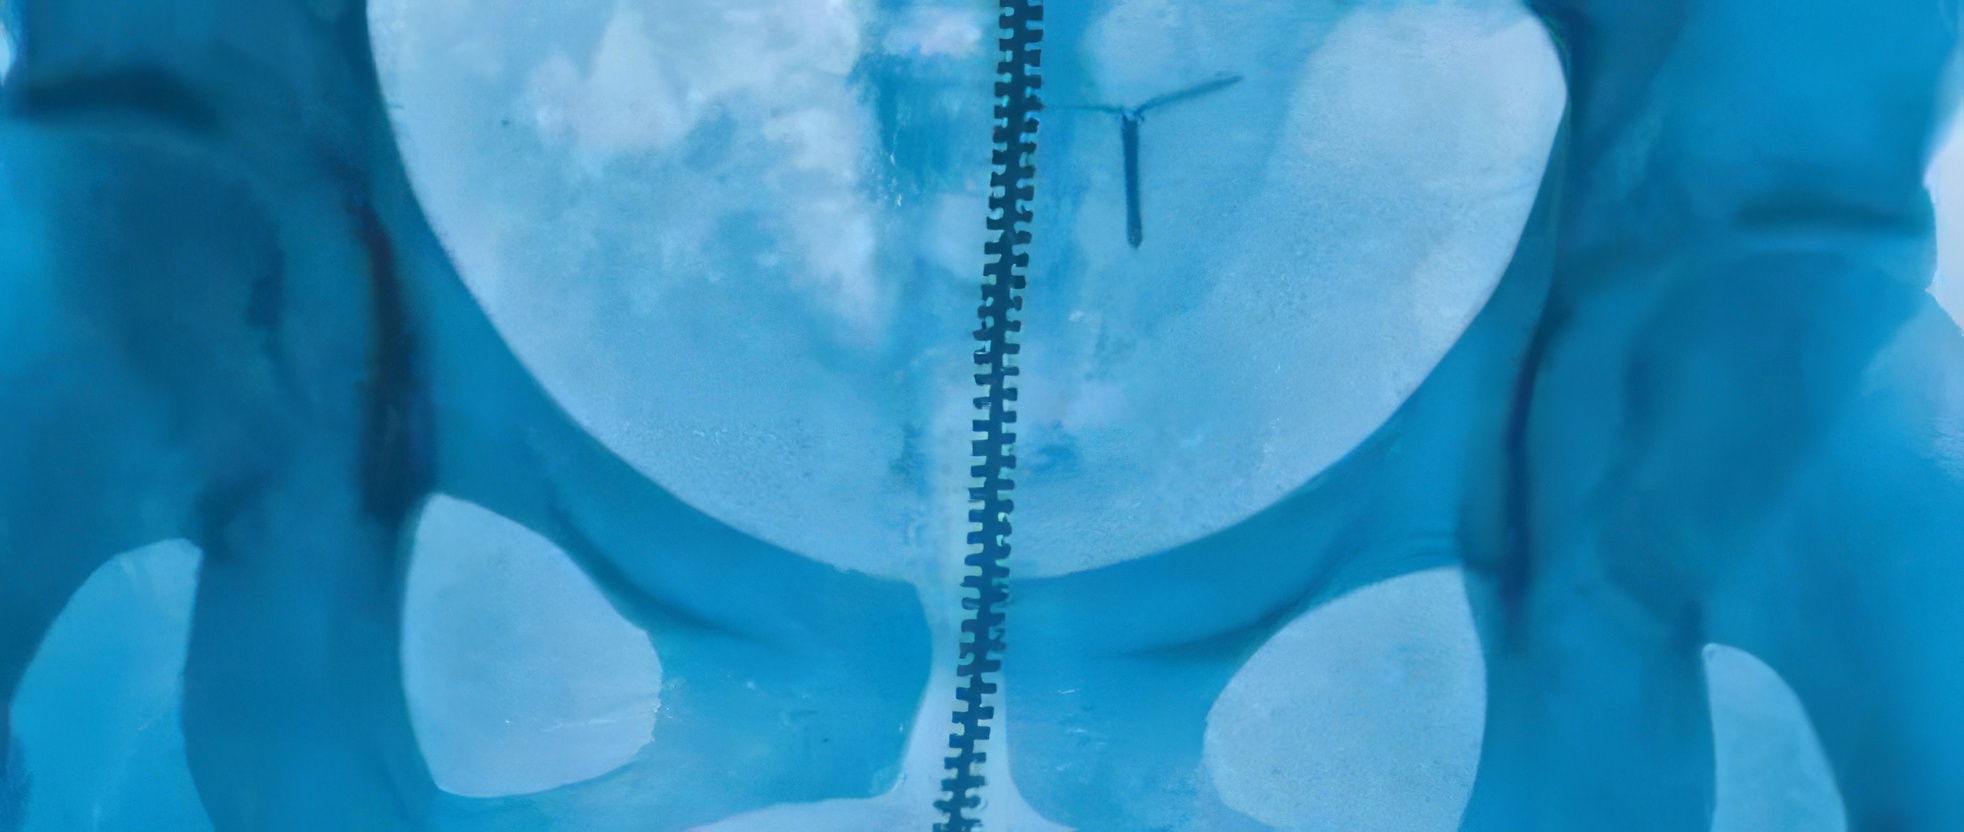

Pour commencer, la pochette de l’album est déjà très originale. Il ne s’agit pas d’un portrait de la chanteuse, mais d’une radiographie, comme celles que l’on passe à l’hôpital. On y voit très clairement le bas du squelette d’une personne : son bassin, sa colonne vertébrale, son coccyx… On devine aussi la fermeture éclair d’un jean, la boucle d’une ceinture, et même un dispositif contraceptif intra-utérin (un stérilet). C’est déjà une image très intime et personnelle.

Mais l’histoire devient vraiment croustillante quand une internaute raconte avoir montré la photo à une amie infirmière. Cette dernière a immédiatement repéré un détail que nous, simples mortels, n’aurions jamais vu. Vous voyez ces petites taches blanches sur la gauche de la colonne vertébrale ? Eh bien, selon l’infirmière, ce n’est rien d’autre que… des matières fécales dans l’intestin. Oui, vous avez bien lu. Des sites de radiologie confirment d’ailleurs que c’est tout à fait normal et courant sur une radio de l’abdomen.